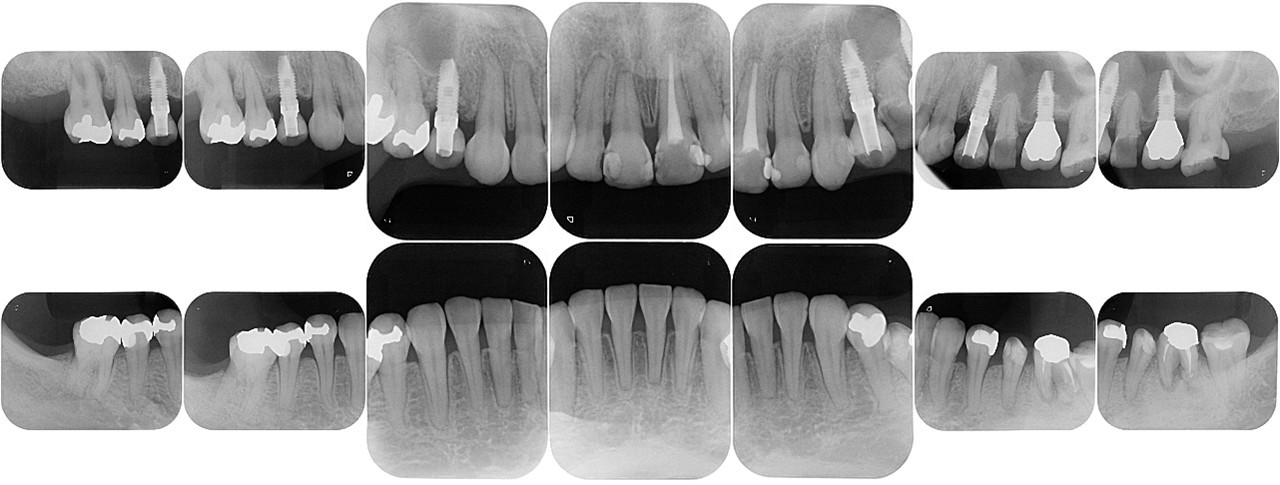

(図19)初診時のレントゲン所見

ほとんどが有髄歯であり無髄歯は左上1番と左下6番のみ左下6番は歯根破折しており抜歯を予定